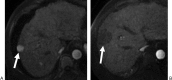

Radiofrequency ablation (RFA) is an alternative therapy for hepatocellular carcinoma and liver metastases when resection cannot be performed or, in the case of hepatocellular carcinoma, when transplant cannot be performed in a timely enough manner to avoid the risk of dropping off the transplant list. RFA has the advantage of being a relatively low-risk minimally invasive procedure used in the treatment of focal liver tumors. This review article discusses the current evidence supporting RFA of liver tumors, as well as the indications, complications, and follow-up algorithms used after RFA.